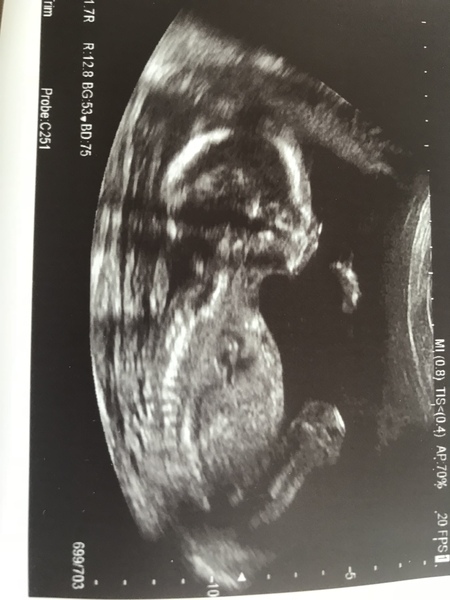

Went for my 20 week scan today. All good, baby very healthy, we found out we are having a little girl. Cried when I saw her little feet (before I was told she was a girl) it was emotional.

It’s a boy. She said everything was fine and was super positive, right up until the end when she said she thought I might have gestational diebetes and to come back for another scan in a month. Totally put a dampener on it for me as I was worried this would happen and I’m blaming myself for putting the weight on and generally being unhealthy.

Aww so happy for you all on recent scans @comps83 wow what a lovely clear scan hope you okay dont stress too much I also have to have the glucose test for the diabietes I still have to wait 2 more weeks for my 20 week scan I will be 20 +4 when I have it cant wait but also feeling very nervous as I still ain't feeling very pregnant dont know if it's normal everyone keeps saying maybe because I have an 11 month old to run after my mind is pre occupied I dont know what to think

:-) new to this thread.. had 20 week scan today (I’m 21 though) and baby is due 13th December!

Everything looks good although kept the gender a secret Grin